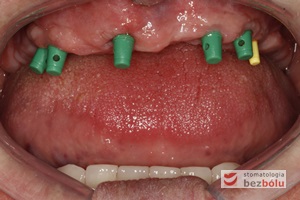

Ekspozycja implantów w szczęce - przesunięcie płata z podniebienia na stronę wargową w celu zwiększenia objętości dziąsła

Ekspozycja implantów w szczęce – przesunięcie płata z podniebienia na stronę wargową w celu zwiększenia objętości dziąsła

Proces pobierania wycisków - transfery wyciskowe do łyżki otwartej przykręcone do implantów

Proces pobierania wycisków – transfery wyciskowe do łyżki otwartej przykręcone do implantów